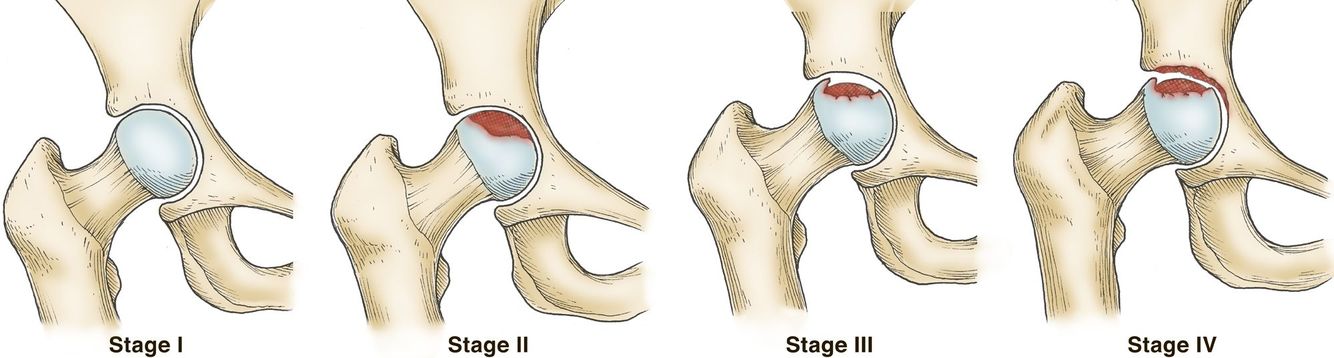

What is Crescent sign of the femur?

Subchondral lucency at the femoral head

Indicates imminent articular collapse requiring arthroplasty

Defines Stage III AVN of femoral head